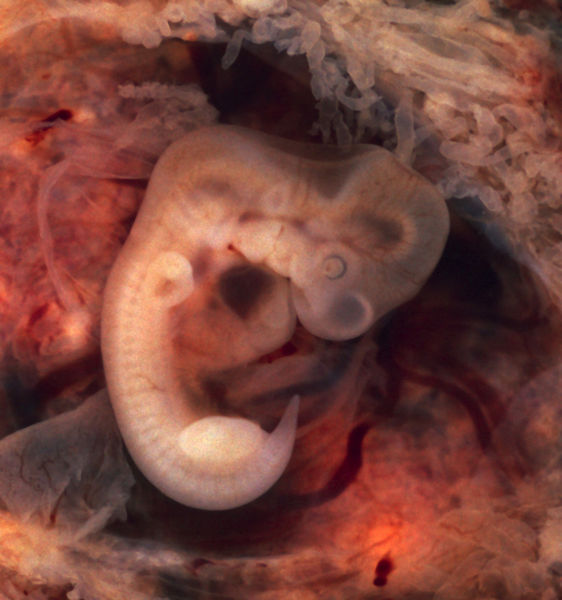

Fotografie + Description: Human Embryo (7th week of pregnancy, 5th week p.o.)

- This photo of an opened oviduct with an ectopic pregnancy features a spectacularly well preserved 10-millimeter embryo. It is uncommon to see any embryo at all in an ectopic, and for one to be this well preserved (and undisturbed by the prosector's knife) is quite unusual.

- Even an embryo this tiny shows very distinct anatomic features, including tail, limb buds, heart (which actually protrudes from the chest), eye cups, cornea/lens, brain, and prominent segmentation into somites. The gestational sac is surrounded by myriad chorionic villi resembling elongated party balloons. This embryo is about five weeks old (or seven weeks in the biologically misleading but eminently practical dating system used in obstetrics).

- The photo was taken on Kodak Elite 200 slide film, with a Minolta X-370 camera and 100mm f/4 Rokkor bellows lens at near-full extension. The formalin-fixed specimen was immersed in tap-water and pinned to a tray lined with black velvet. The exposure was 1/4 second at f/8.